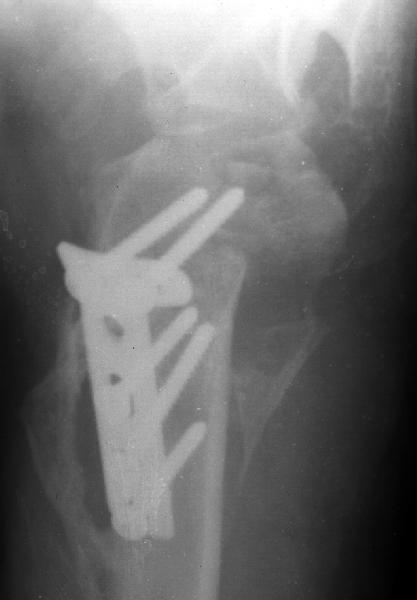

Мужчина 25 лет 16 августа 2002 г. в автоаварии получил перелом шейки плеча (снимок 1); 5 сентября в городской больнице выполнен остеосинтез пластинкой (снимок 2).К настоящему времени попал к нам на разработку ввиду выраженной контрактуры плечевого сустава. В течение последнего месяца беспокоят умеренные боли в области плечевого сустава, усиливающиеся при разработке, еще и торчит край пластинки. Нынешняя рентгенологическаякартина на снимках 3 и 4. Головка плеча уменьшается, сращение сомнительное.Кроме удаления пластинки, что еще на сегодня целесообразно сделать?Заранее спасибо.

The current xrays indicate failure of the implant with losening. I would make sure there was no evidence of infection ( exam,ESR,CRP etc.) . I would agree with implant removal . I think this would be a suitable case for a circular ring fixator and compression, either a standard IIizarov or Taylor Spatial frame would be appropriate. I note from your previous cases that you have a high level of experience with this method.